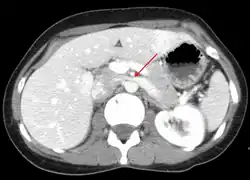

Thrombosis in the left renal vein associated with dilation